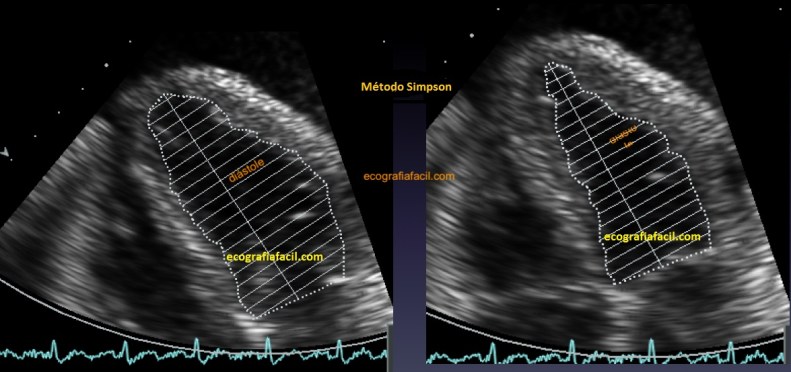

Para la valoración de la FEVI (fracción de eyección del VI) tenemos 3 métodos: el primero de ellos es cualitativo y consiste en sacar una impresión general de la contracción global. Recuerda que por debajo del 50% ya hablamos de FEVI deprimida. El segundo es el método Teichold, consistente en hacer una resta entre el diámetro del VI en diástole y sístole en el paraesternal eje largo y que ya vimos en un post anterior. El tercero es el método Simpson biplano, para el que necesitamos obtener el área del VI en el 4 cámaras y en el 2 cámaras (figura 25). El equipo hará sus cuentas para ofrecernos una valoración numérica. Todos los datos que obtengamos de los 3 métodos no deben ser discrepantes entre sí aunque haya ligeras variaciones. Si obtenemos una FEVI visual y por Teich del 65% y el método Simpson nos habla de 30%, evidentemente algo está mal.

For the assessment of LVEF (ejection fraction of the LV) we have 3 methods: the first one is qualitative and consists of taking a general impression of the global contraction. Remember that below 50% we already talked about depressed LVEF. The second is the Teichold method, consisting of subtracting the diameter of the LV in diastole and systole in the parasternal long axis, which we saw in a previous post. The third is the Simpson biplane method, for which we need to obtain the VI area in the 4 chambers view and in the 2 chambers view (figure 25). The team will make their accounts to offer us a numerical valuation. All the data we obtain from the 3 methods should not be discrepant with each other although there are slight variations. If we obtain a visual LVEF and Teich 65% and the Simpson method tells us 30%, obviously something is wrong.